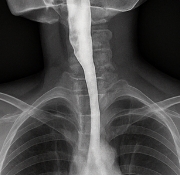

의사는 환자의 식도염 증상과 병력을 확인한 뒤 내시경 검사를 시행합니다.

- 위내시경: 점막 손상, 염증 정도 확인

- 24시간 산도 검사: 위산 역류 여부 측정

- 조직 검사: 감염성 원인 여부 확인

정확한 진단이 있어야 식도염 증상 치료가 효과적입니다.